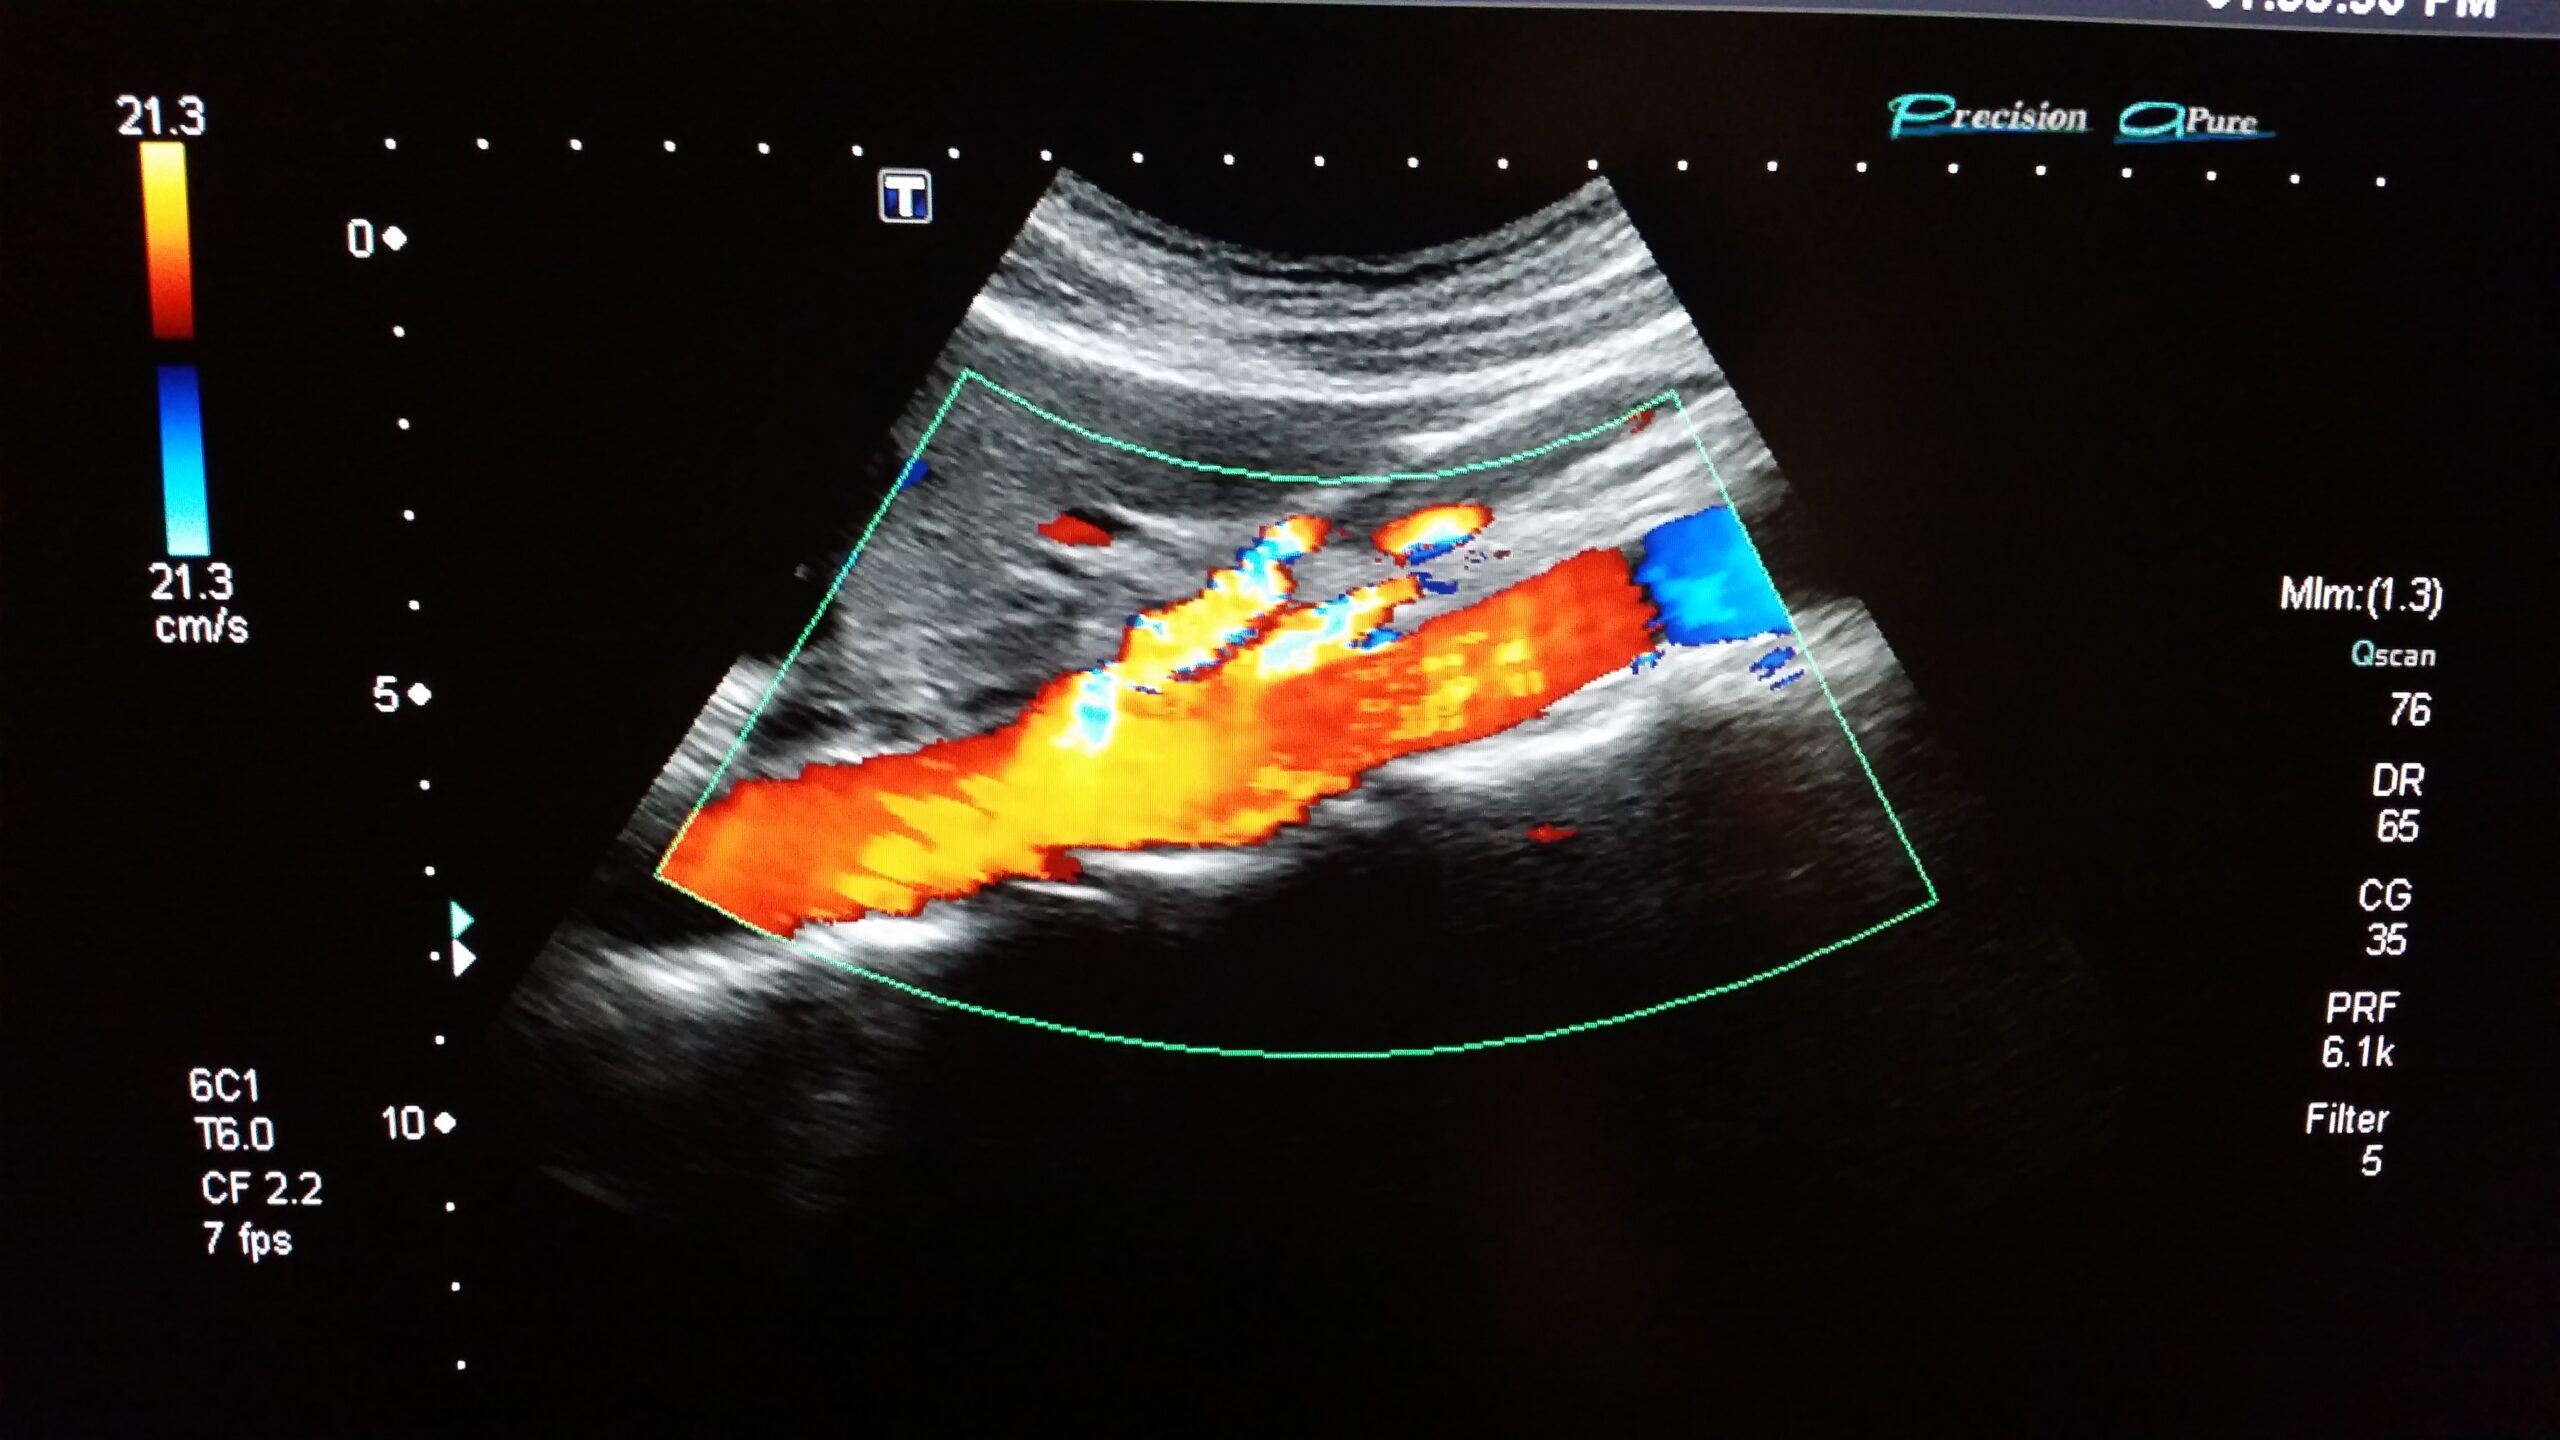

- Doppler de pene